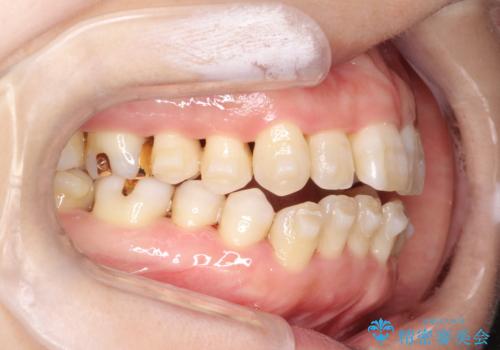

- 上下の前歯の開き(開咬)と上下前歯にガタつき(叢生)が見られます。

マウスピース矯正ではメカニクス的に開咬へのアプローチが容易です。

インビザラインの特色を生かした歯牙移動計画を作成し、非抜歯にて治療を行いました。